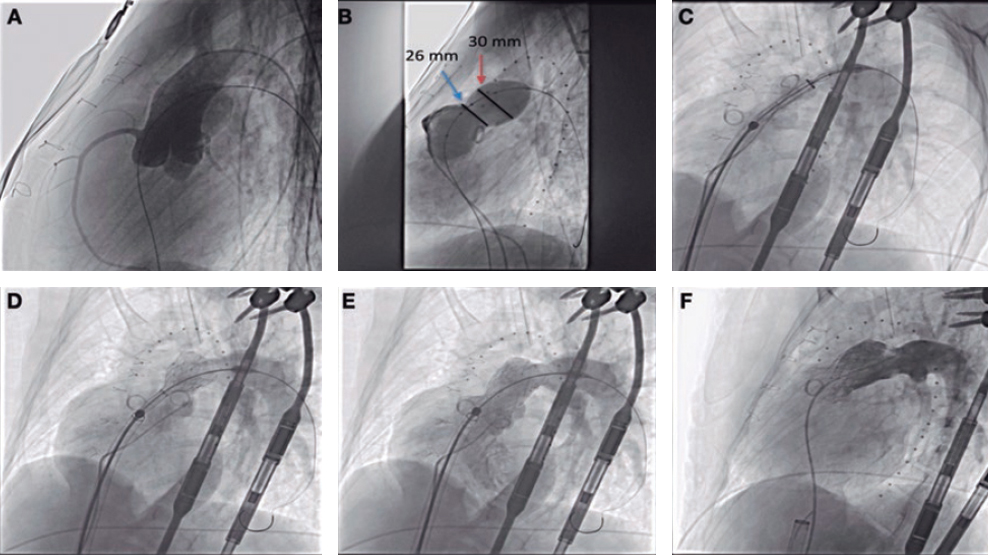

Creation of an arteriovenous shunt

After the infarction volume overload was attempted through the creation of an arteriovenous shunt by connecting a branch of the pulmonary artery to the aorta using a Dacron tube graft. This procedure was performed with clamping and without extracorporeal circulation.